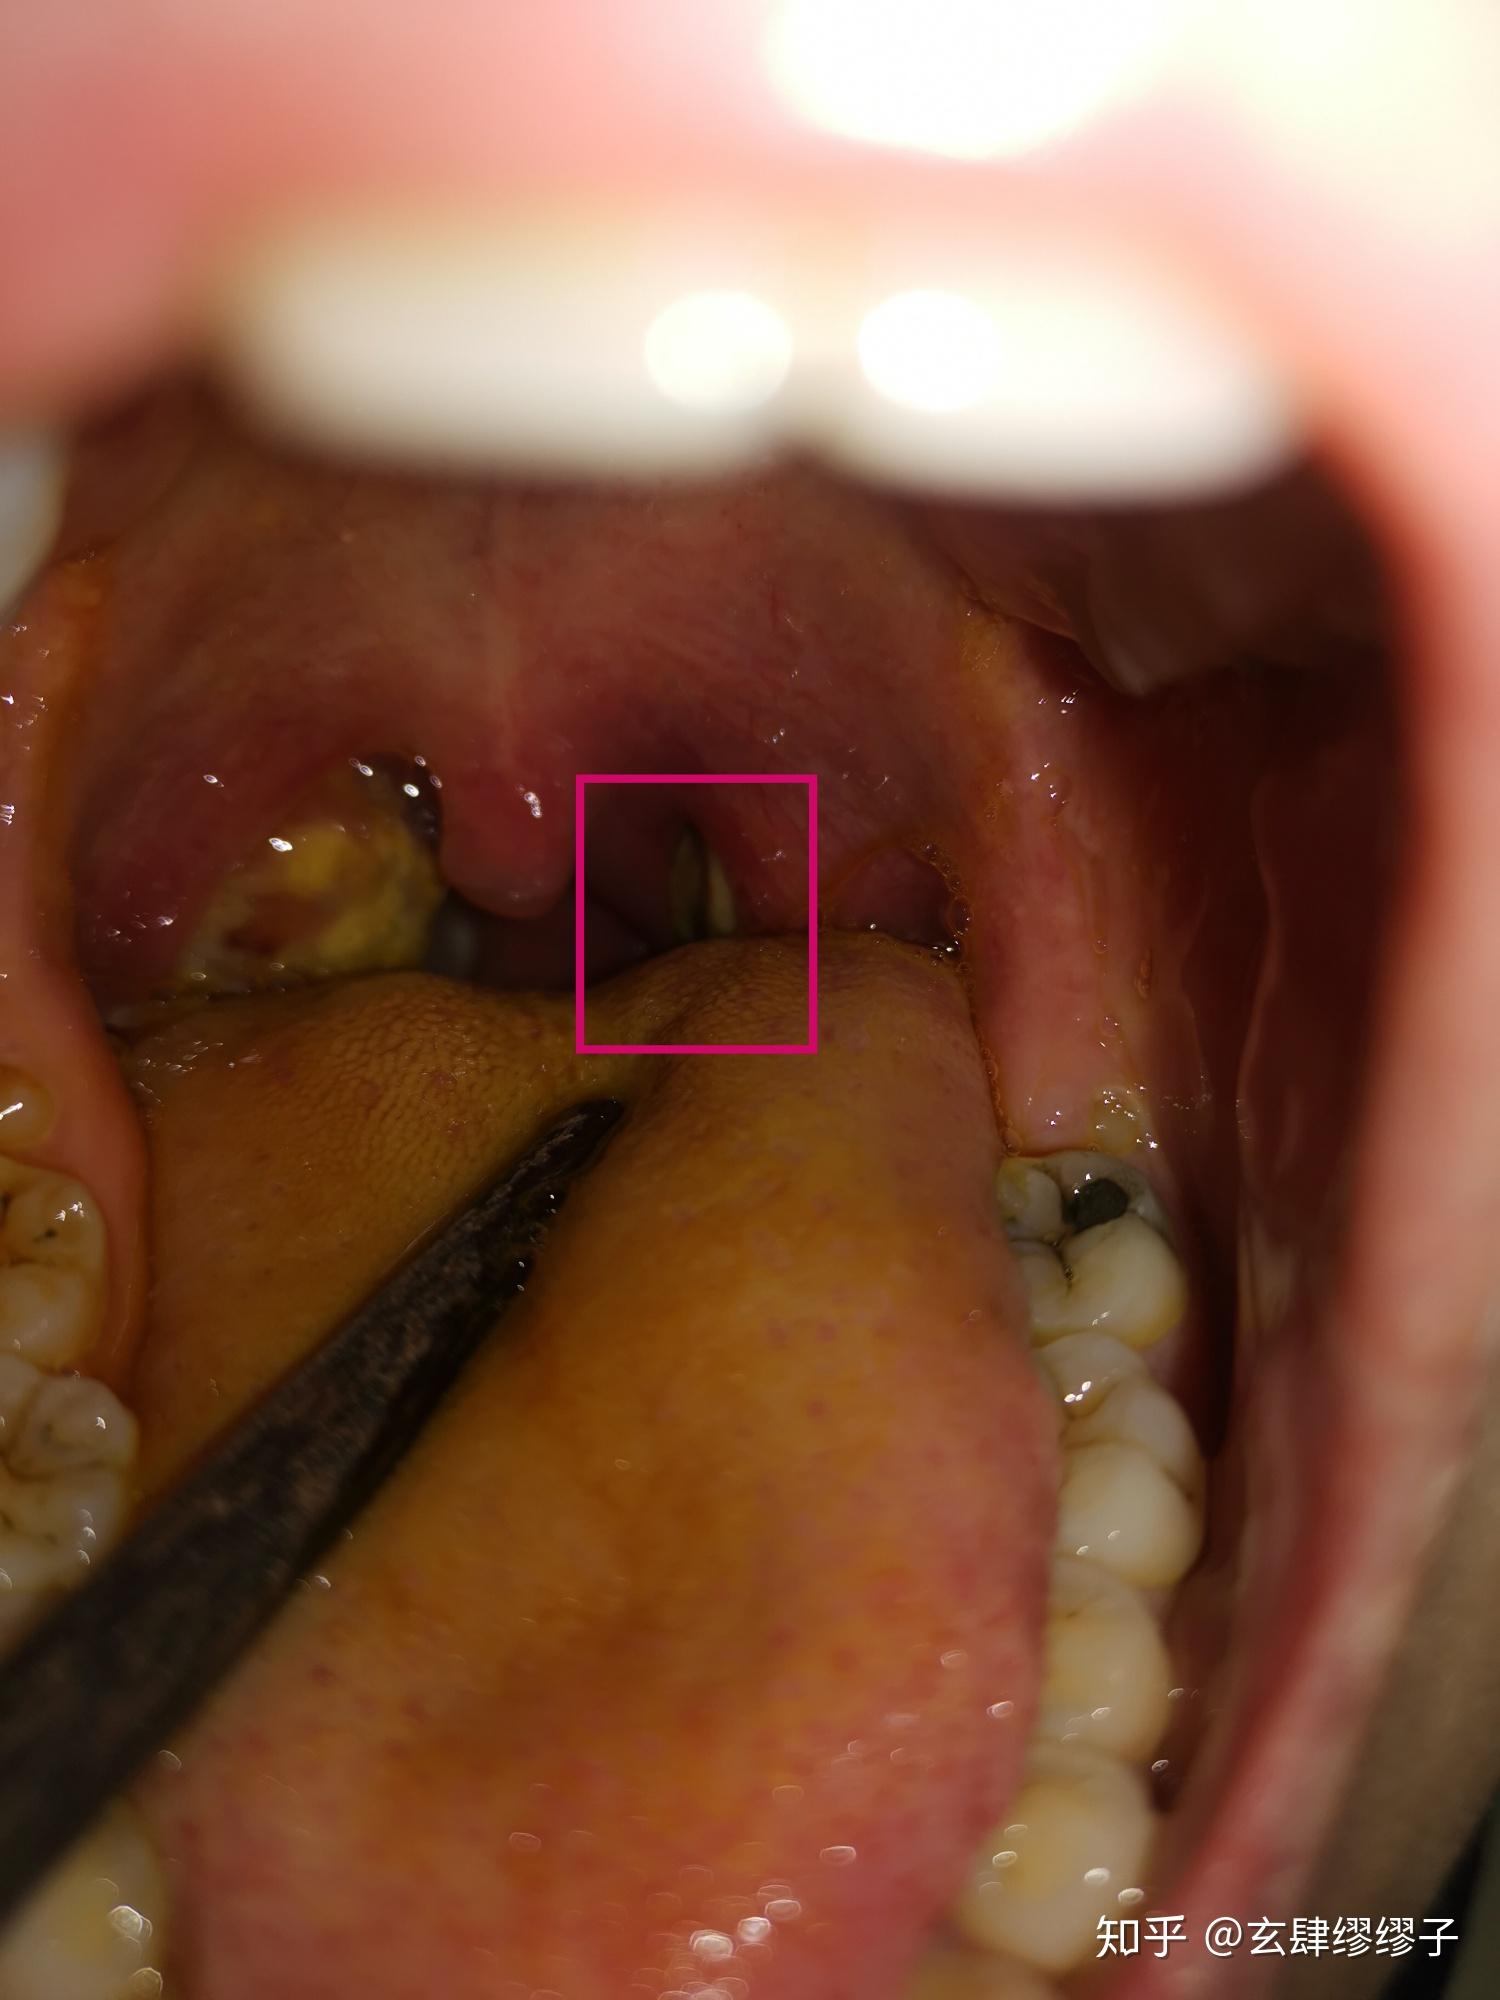

急性化脓性扁桃体炎的疼痛级别? - 知乎

图片尺寸1500x2000